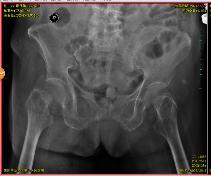

术前X光片

阿婆姓廖,家住坪地街道坪东社区,今年已经是101岁高龄。日前在家中不慎摔倒,由家属呼叫120救护车紧急送入区六院骨科,被确诊为右股骨颈骨折。